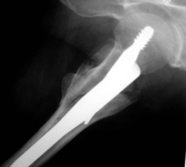

Seitlich wurde der Nagel fehlpositioniert, was

beim Belasten zum Auswandern führte. Mit dem Zielgerät

nach Asche wäre dies nicht passiert.